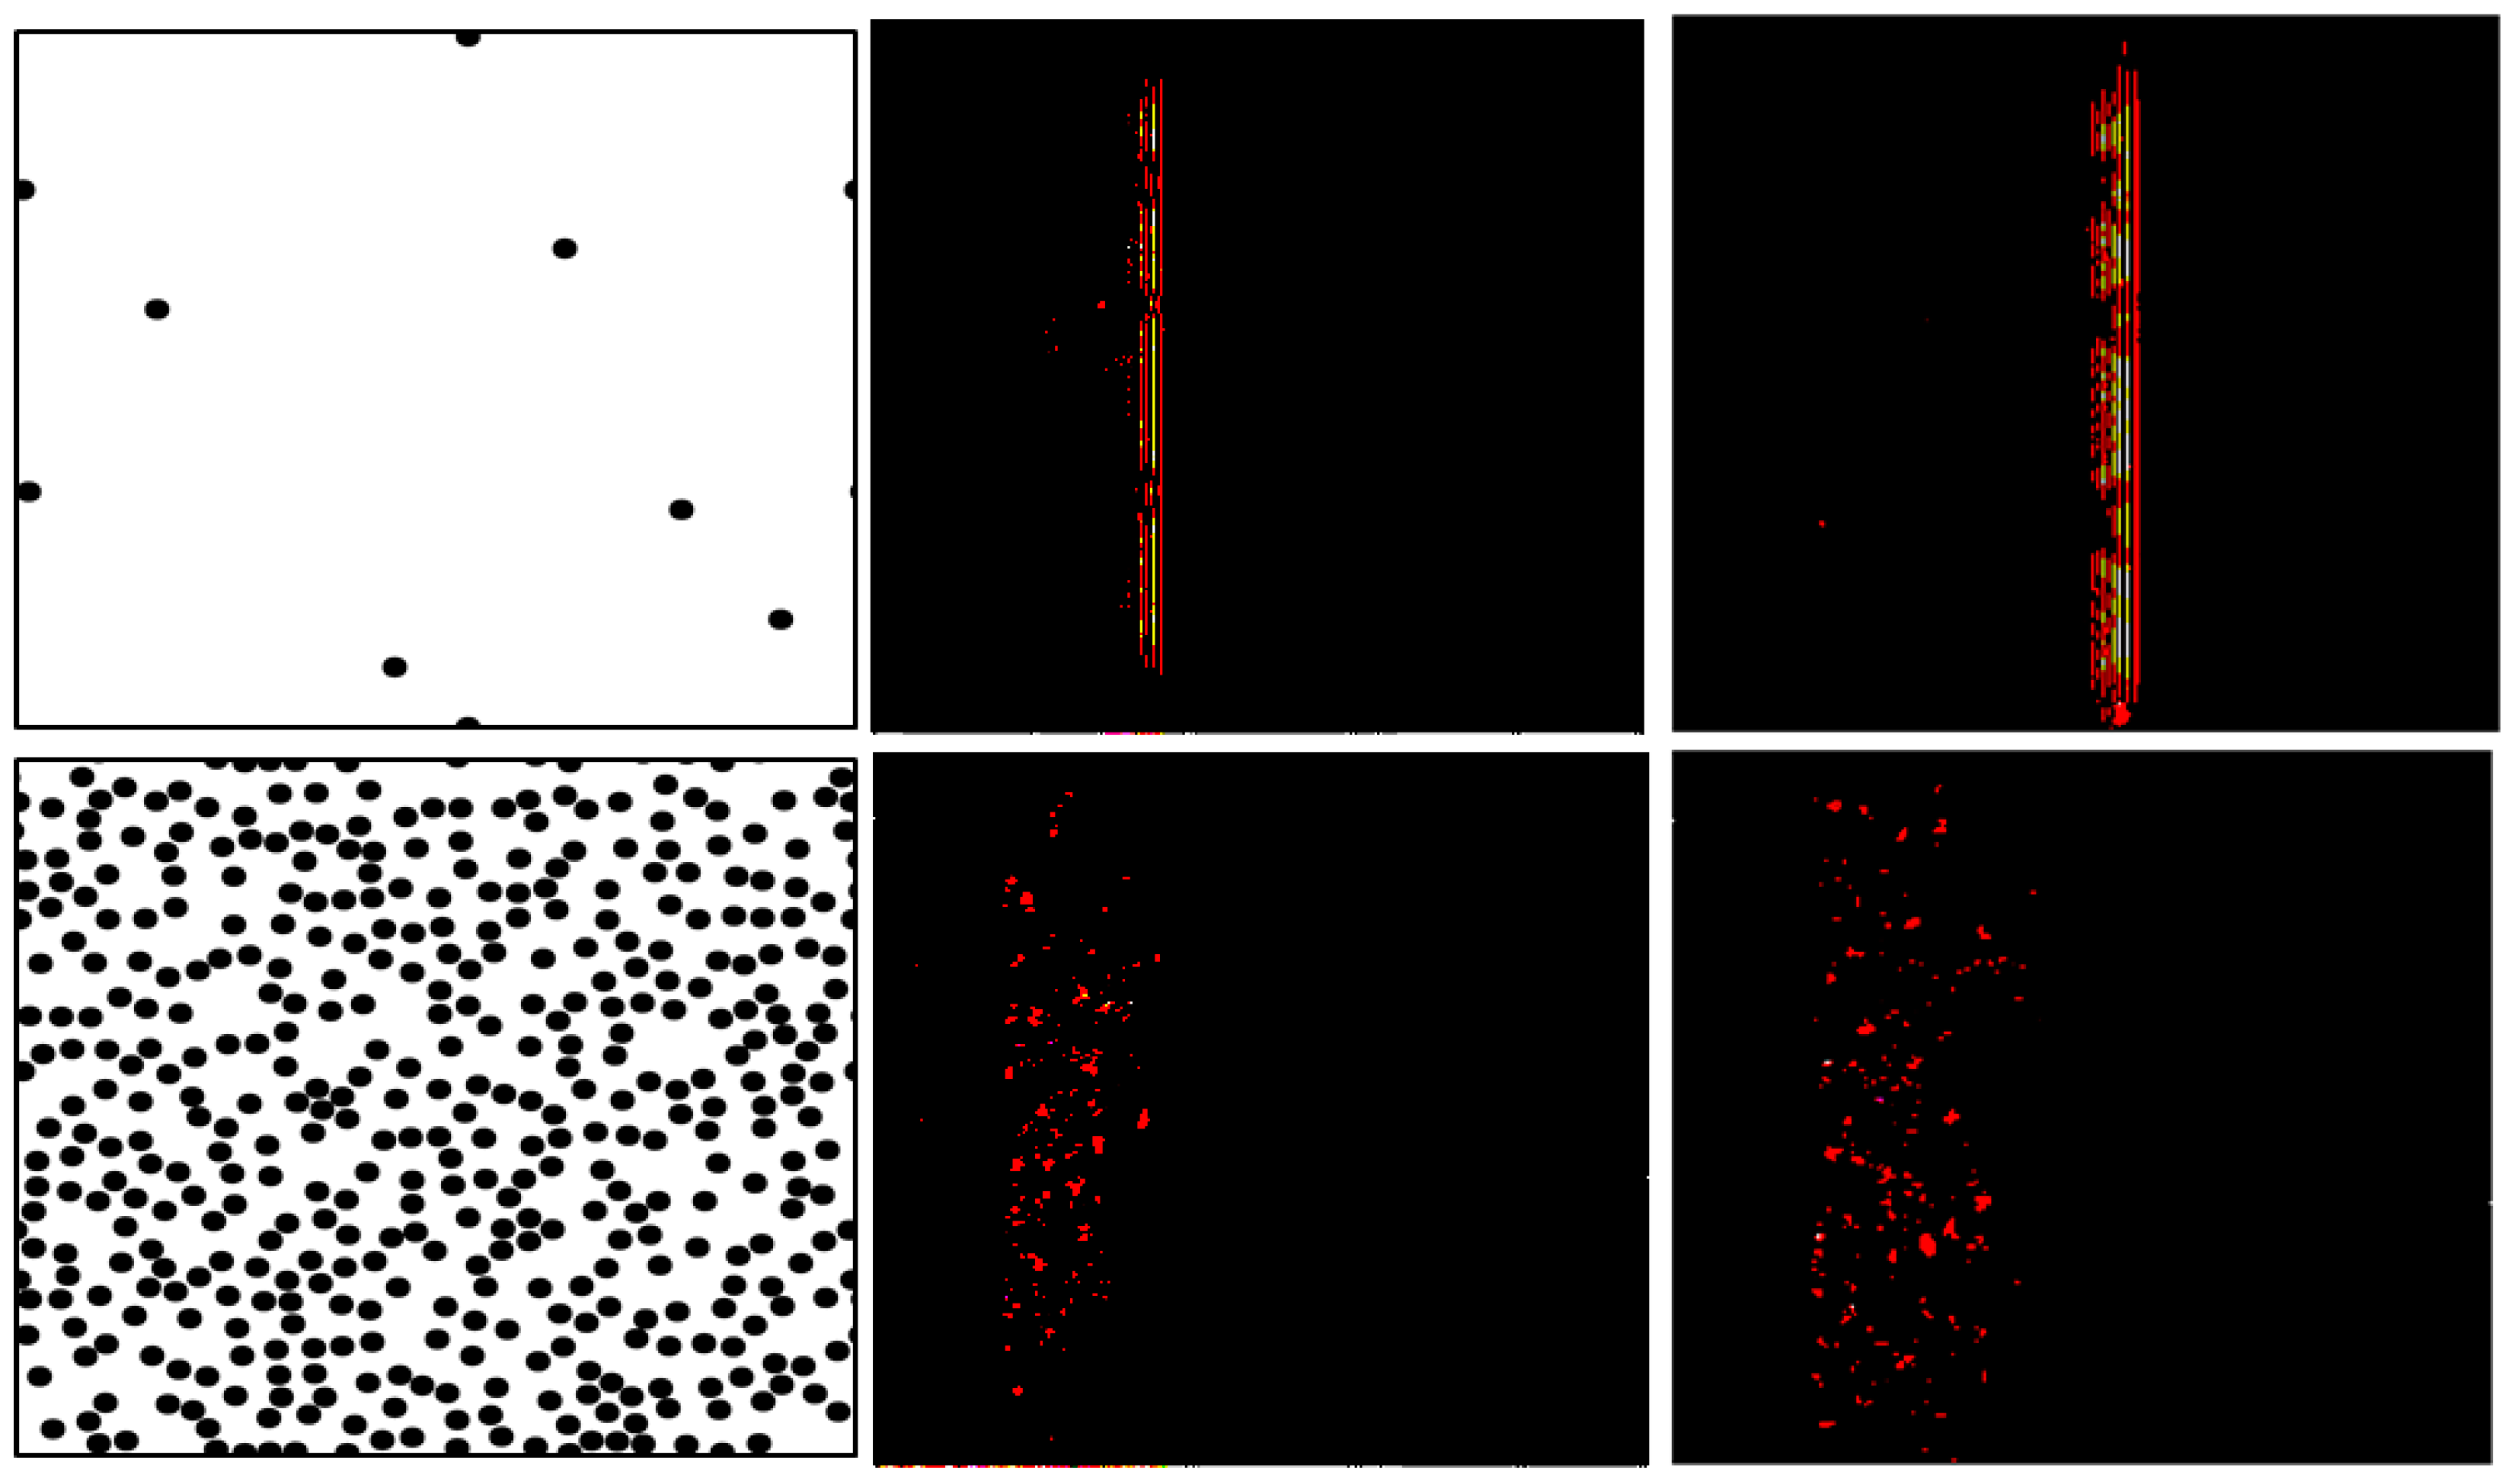

- Mohanty, K.; Blackwell, J.; Egan, T.; Muller, M. Characterization of the Lung Parenchyma Using Ultrasound Multiple Scattering. Ultrasound Med. Biol. 2017, 43, 993–1003. [Google Scholar] [CrossRef] [PubMed]